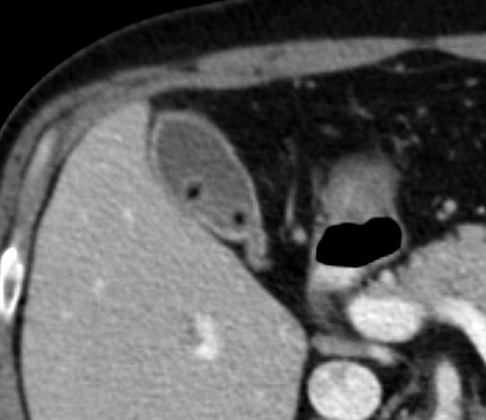

Calcul arrondie hyperdense a

infundibulum de la vesicule biliaire . Vesicule est

distendue , paroi epais et oedeme ( cholecystite ) .

Image TDM , coupe axiale , contrast intraveineuse |

Meme cas en coupe frontale

(coronal ) |